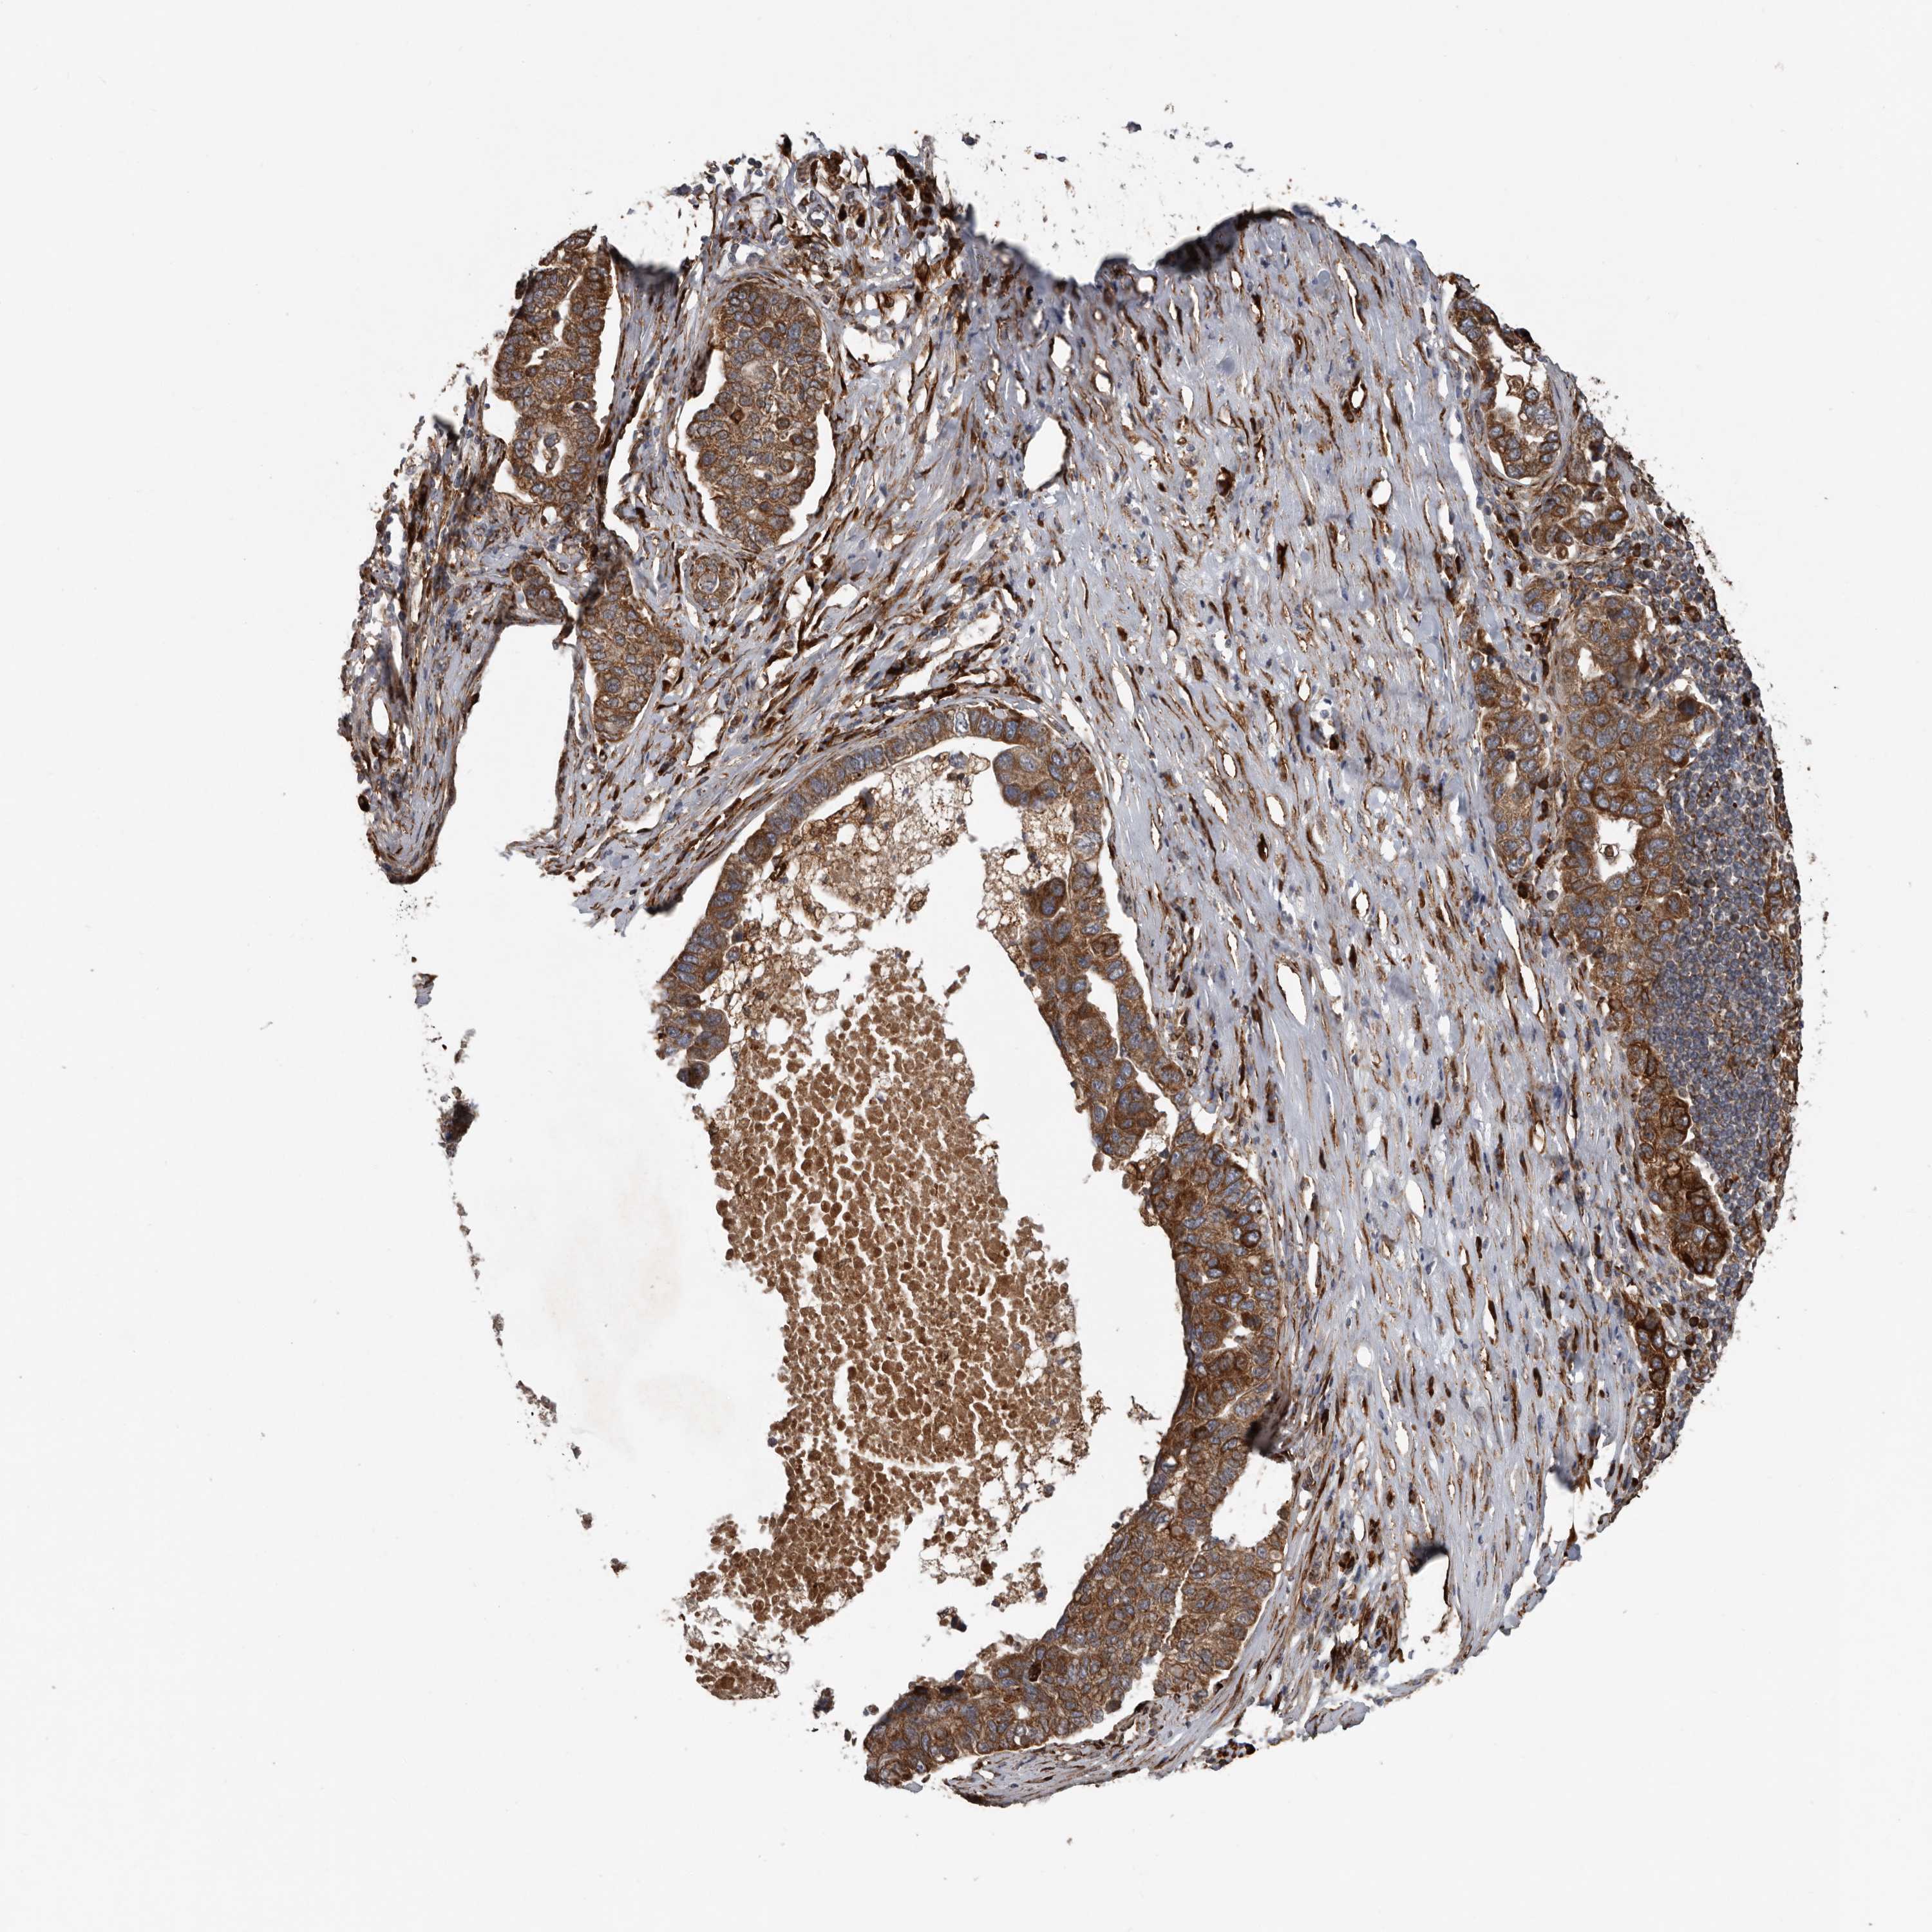

PANCREATIC CANCER - Protein expressioni

A mouse-over function shows sample information and annotation data. Click on an image to view it in a full screen mode. Samples can be filtered based on level of antibody staining by selecting one or several of the following categories: high, medium, low and not detected. The assay and annotation is described here.

Note that samples used for immunohistochemistry by the Human Protein Atlas do not correspond to samples in the TCGA dataset.

Antibody stainingi

Antibody staining in the annotated cell types in the current human tissue is reported as not detected, low, medium, or high, based on conventional immunohistochemistry profiling in selected tissues. This score is based on the combination of the staining intensity and fraction of stained cells.

Each image is clickable and will lead to virtual microscopy that enables deeper exploration of all samples and also displays staining intensity scores, fraction scores and subcellular localization as well as patient and tissue information for each sample.

Antibody HPA028355

Antibody HPA028357

Staining

High

Medium

Low

Not detected

Intensity

Strong

Moderate

Weak

Negative

Quantity

>75%

75%-25%

<25%

None

Location

Nuclear

Cytoplasmic/membranous

Cytoplasmic/membranous,nuclear

Adenocarcinoma, NOS